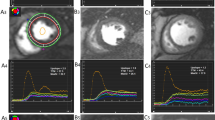

For the analysis of ShMOLLI T1-maps, the LV myocardium of the mid ventricular short axis slice acquired at baseline was contoured by two operators (EL, SKP), using dedicated software, as previously described [26], providing a single average myocardial T1 value from the whole slice of T1 map per each individual with consensus of two operators. T1-maps were assessed for quality in three ways: examination of the T1-map, the raw T1 images and R2 maps; ~11% of segments were excluded due to any combination of: off-resonance artifacts, partial-volume effects, poor T1 fit on the R2 maps, patient movement or low signal to noise, similar to previous publications using T1-mapping from our center [27]. The myocardial T1 value from the stress mid-ventricular ShMOLLI non-contrast T1-map was obtained and compared to the non-contrast T1 at baseline (Fig.1 ).

Representative examples of rest and stress T1 maps. Normal control with a resting native T1-map, 1174 ms; b corresponding stress T1-map, 1271 ms. T2DM patient with c resting native T1-map, 1177 ms; d corresponding stress T1-map, 1195 ms. Values in graphic indicate the average mid-left-ventricular myocardial T1 values

Changes in rest and adenosine stress T1 mapping